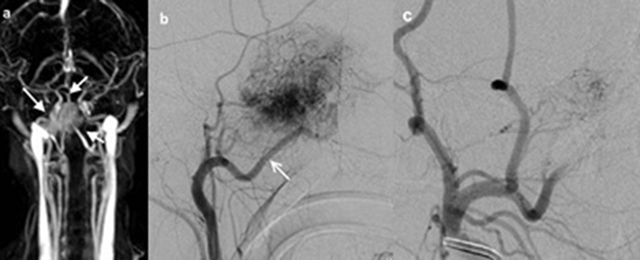

Figure 2

10-year-old male patient (patient 3), (a) TWIST-MR angiography of the patient showed bilobule hypervasculer mass on the right side (white arrows). (b) Selective right carotid artery angiography shows that JNA is supplied with the right internal maxillary artery (white arrow). (c) It is observed that the opacification of JNA mainly dissappeared in the angiography display obtained after the internal maxillary artery was embolized with microcoil.

The evaluation of the available carotid TOF MR angiography studies of two patients and the TWIST-MR angiography of one patient showed hypervasculer masses (Figure 2) and the blood supply to the tumor to be mainly from the internal maxillary branch of the external carotid artery. In these angiographic studies, tumors didn’t seem to exhibit mass effect on adjacent vascular structures.

JNA is frequently supplied by the sphenopalatine and the maxillary arteries, especially in its early stage. Vascular supply from other external carotid artery branches or from the vertebral and internal carotid artery branches is also possible [11]. In this study, three patients were evaluated with additional MR angiography studies (two with TOF MR angiography and one with TWIST MR angiography), and the vascular supply to the tumor was from the external carotid artery branches in all three cases, as shown by digital subtraction angiography.